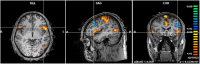

The neural correlates of software programming skills have been the target of an increasing number of studies in the past few years. Those studies focused on error-monitoring during software code inspection. Others have studied task-related cognitive load as measured by distinct neurophysiological measures. Most studies addressed only syntax errors (shallow level of code monitoring). However, a recent functional MRI (fMRI) study suggested a pivotal role of the insula during error-monitoring when challenging deep-level analysis of code inspection was required. This raised the hypothesis that the insula is causally involved in deep error-monitoring. To confirm this hypothesis, we carried out a new fMRI study where participants performed a deep source-code comprehension task that included error-monitoring to detect bugs in the code. The generality of our paradigm was enhanced by comparison with a variety of tasks related to text reading and bugless source-code understanding. Healthy adult programmers (N = 21) participated in this 3T fMRI experiment. The activation maps evoked by error-related events confirmed significant activations in the insula [p(Bonferroni) < 0.05]. Importantly, a posterior-to-anterior causality shift was observed concerning the role of the insula: in the absence of error, causal directions were mainly bottom-up, whereas, in their presence, the strong causal top-down effects from frontal regions, in particular, the anterior cingulate cortex was observed.